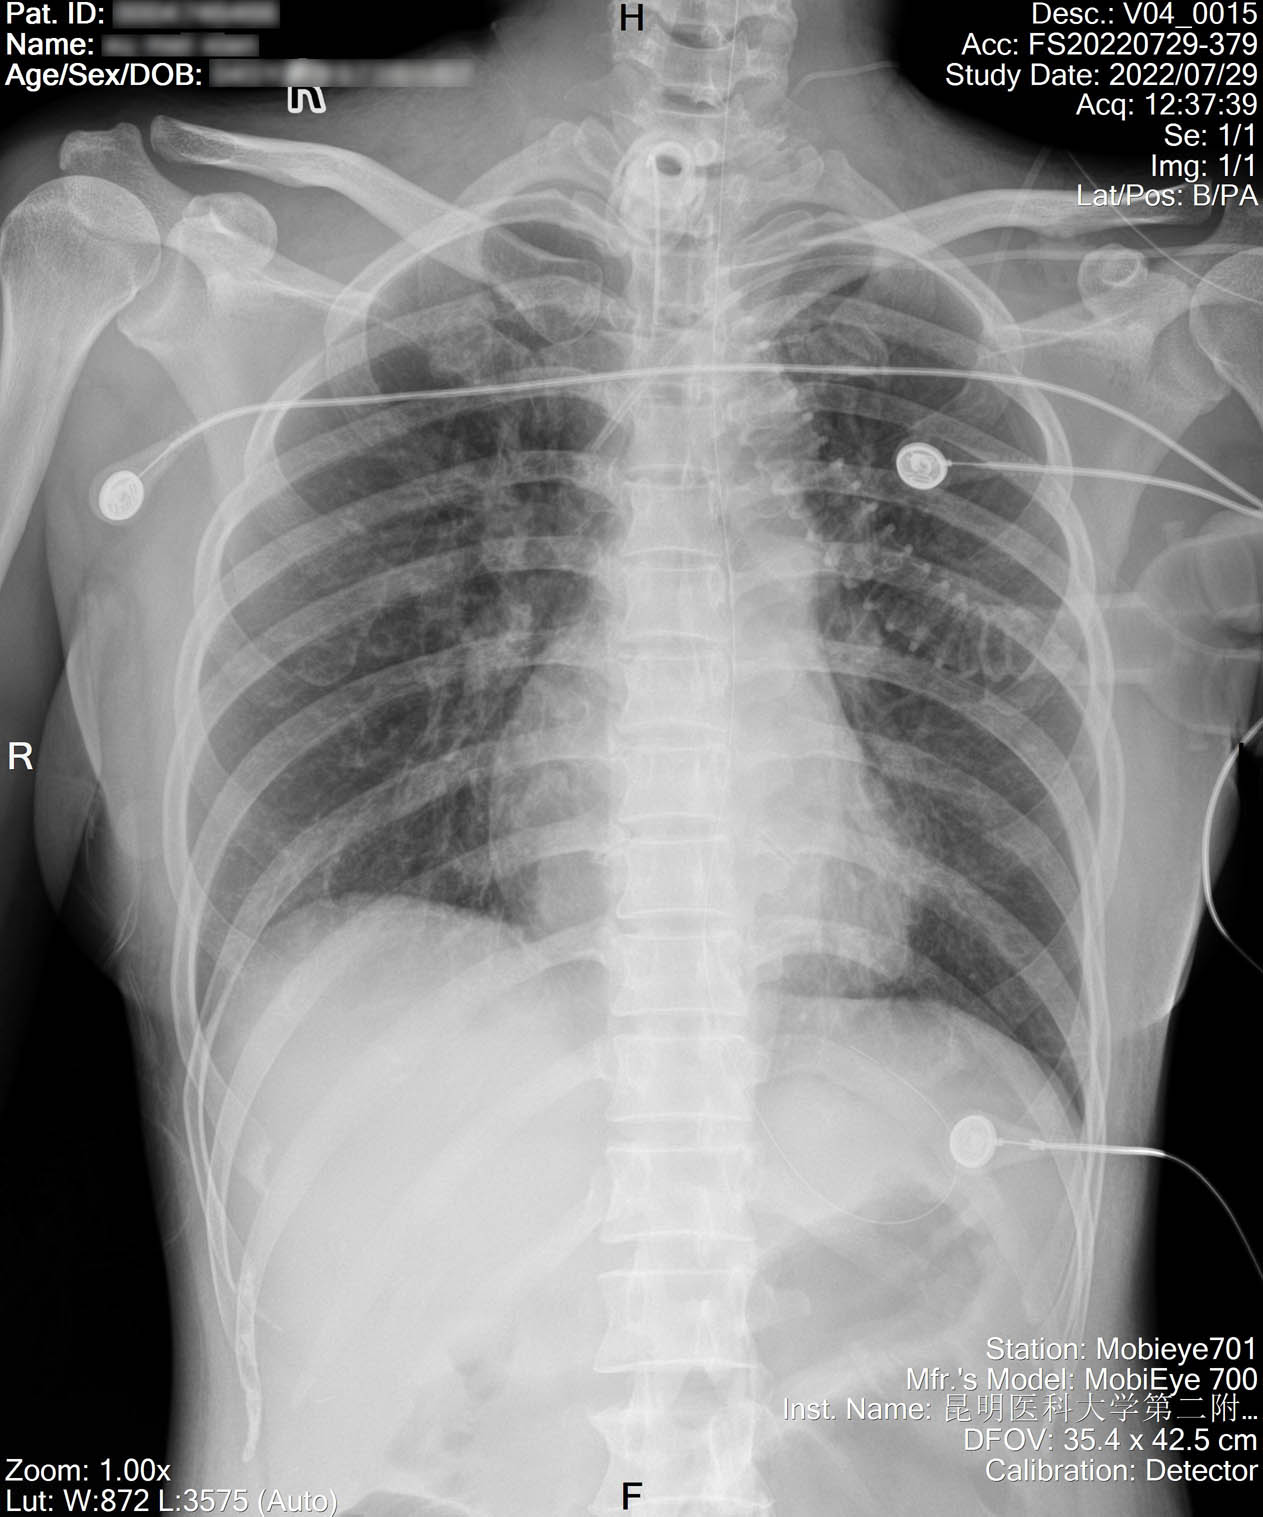

2022-07-19_胸片